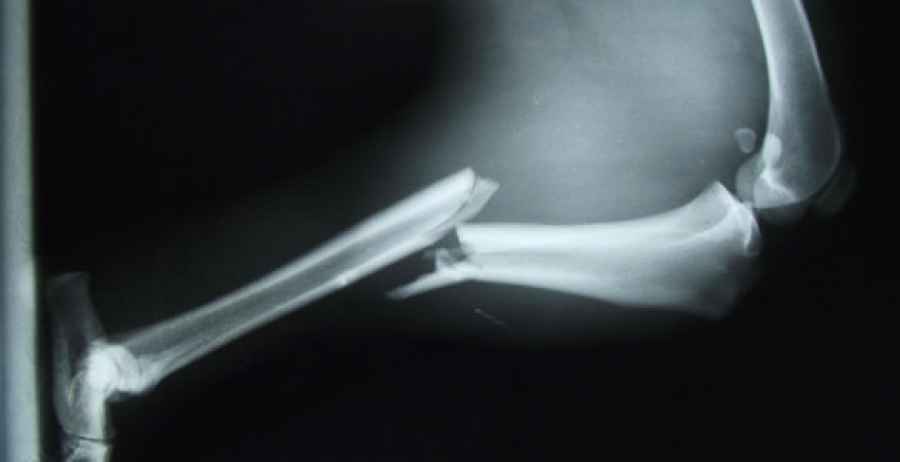

La osteoporosis es una enfermedad caracterizada por la pérdida progresiva de la densidad de los huesos y, en consecuencia, por un mayor riesgo de fracturas óseas. Una enfermedad que afecta principalmente a las personas mayores de 50 años, sobre todo mujeres –la prevalencia es hasta cuatro veces mayor en la población femenina que en la masculina– y que constituye una seria amenaza no solo para la calidad de vida de los pacientes, sino incluso para su esperanza de vida. De ahí la importancia de adoptar hábitos de vida saludables, ya desde la infancia, para prevenirla. Y asimismo, de tomar suplementos con calcio y/o vitamina D para fortalecer los huesos y reducir el riesgo de fracturas. Pero, ¿esto es realmente así? Pues según un estudio llevado a cabo por investigadores del Primer Centro Hospitalario de Tianjin (China), no.

Entonces, ¿en qué quedamos? ¿Hay que tomar o no estos suplementos? Pues para averiguarlo, los autores llevaron a cabo una revisión o ‘metanálisis’ de los resultados alcanzados en 33 grandes ensayos clínicos desarrollados con la participación de 51.145 personas mayores de 50 años. Y lo que vieron es que daba igual que los participantes tomaran suplementos, placebo o, simplemente, ‘nada’: el riesgo de sufrir una fractura, ya fuera de cadera, de una vértebra o de cualquier otro hueso del cuerpo, resultó similar en los tres casos.

Una de cada tres mujeres

Se estima que, cumplidos los 50 años, hasta una de cada tres mujeres y uno de cada cinco varones acabarán padeciendo una fractura por culpa de la osteoporosis. Sin embargo, y a tenor de las nuevas evidencias, parece que la toma de suplementos con calcio y/o vitamina D no ayuda a evitar que esto pase.